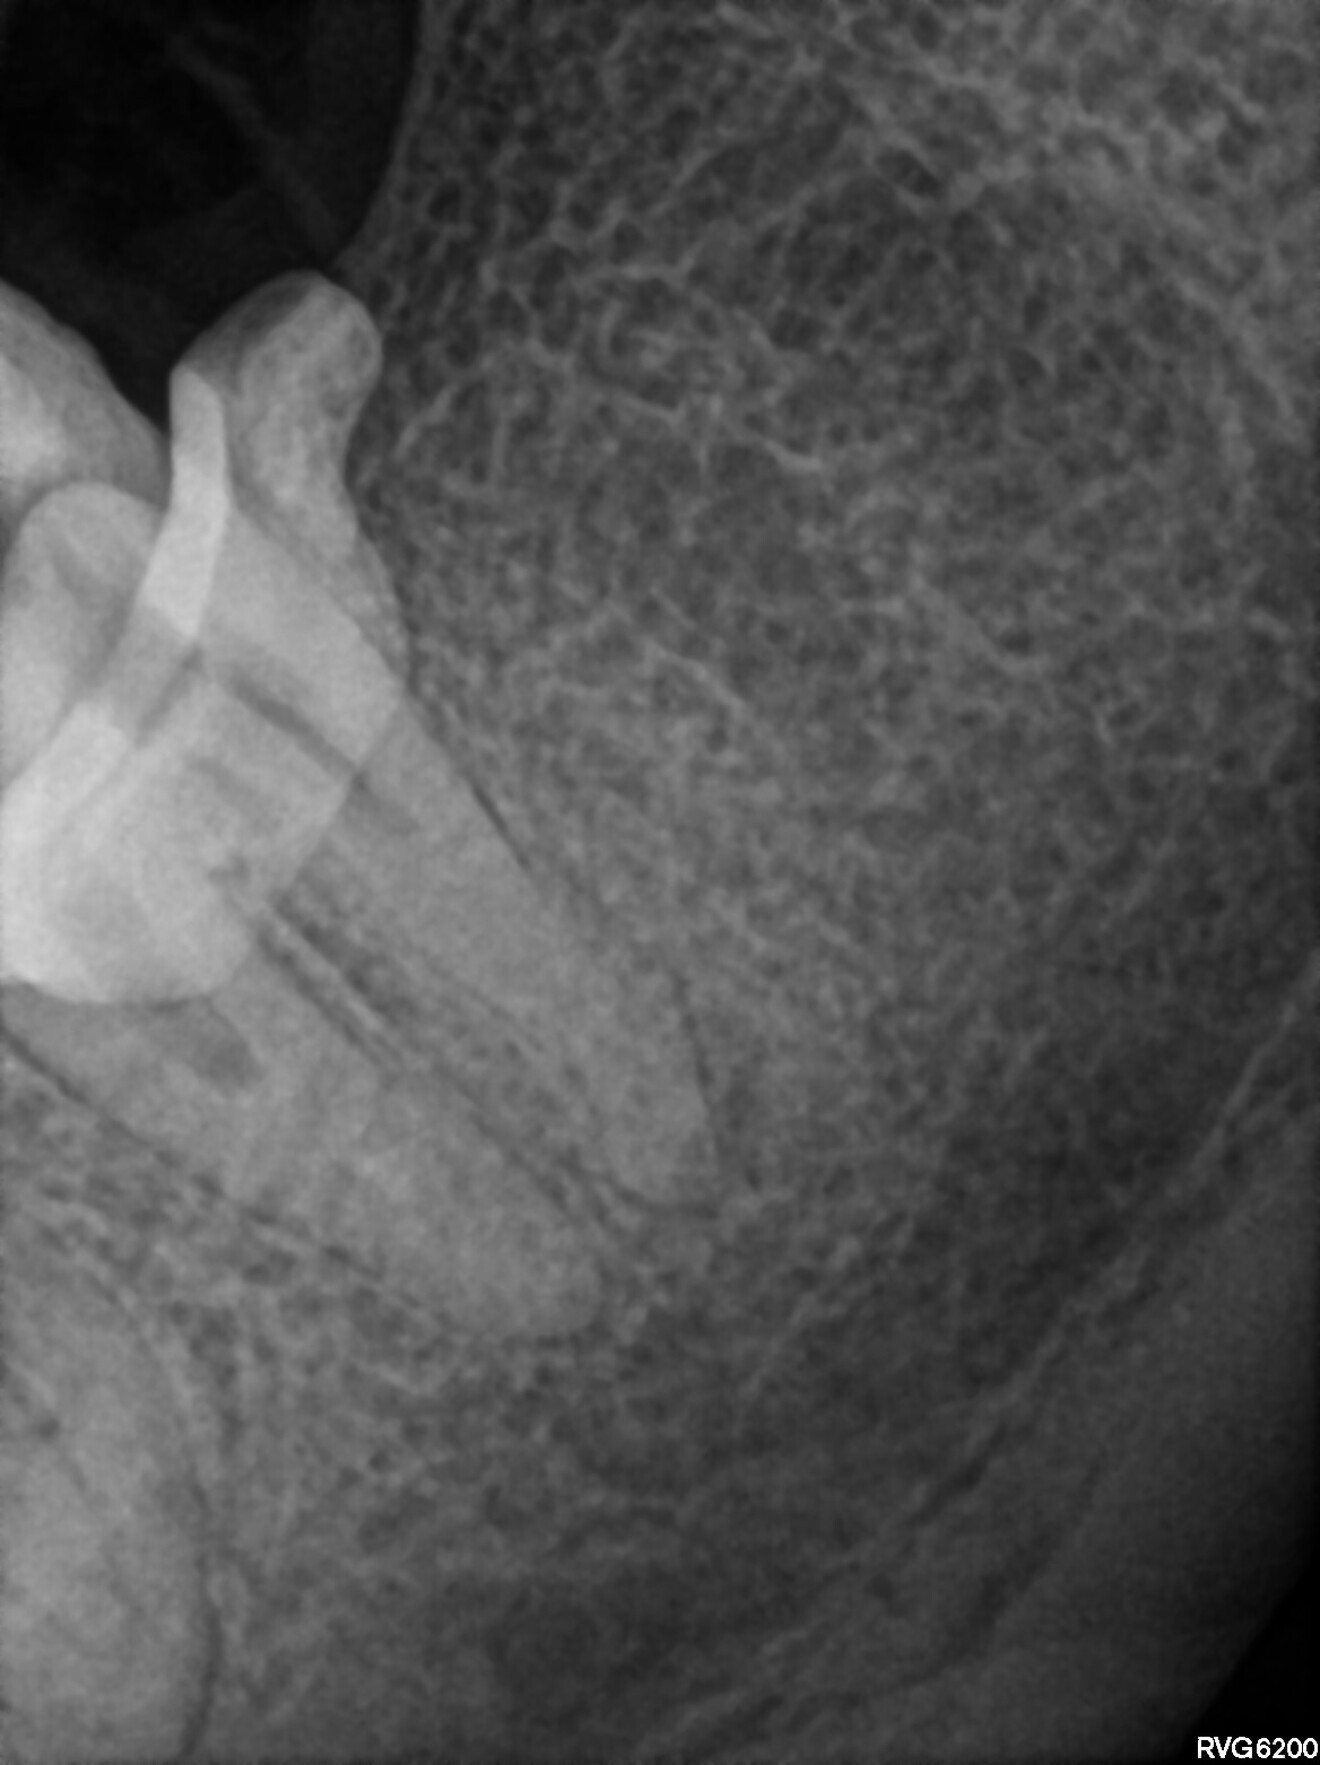

A 56-year-old patient was referred to Dr Witkowski’s clinic for endodontic treatment of tooth #38. Owing to the anatomical situation and reduced possibility of mouth opening, a conventional approach was difficult. A radiograph was performed, and the anatomical structures were examined (Fig. 21). A treatment protocol was created.

An access cavity had already been created by the referring dentist. During visualisation of the pulp chamber (Fig. 22), remnants of the pulp were identified. In order to properly identify canal orifices, cleaning of the pulp chamber was necessary. This is standard protocol for every endodontic treatment, and it is very important in order not to transport debris from the pulp chamber to canal space. This procedure was done using an Er,Cr:YSGG laser with a wavelength of 2,780 nm (Waterlase, BIOLASE) and RFPT5-10 tip (Fig. 23). After this procedure, which should be done according to the protocol of 1 minute of continuous activation and 1 minute of rest (Fig. 24), the operator can start the instrumentation protocol.

Fig. 21